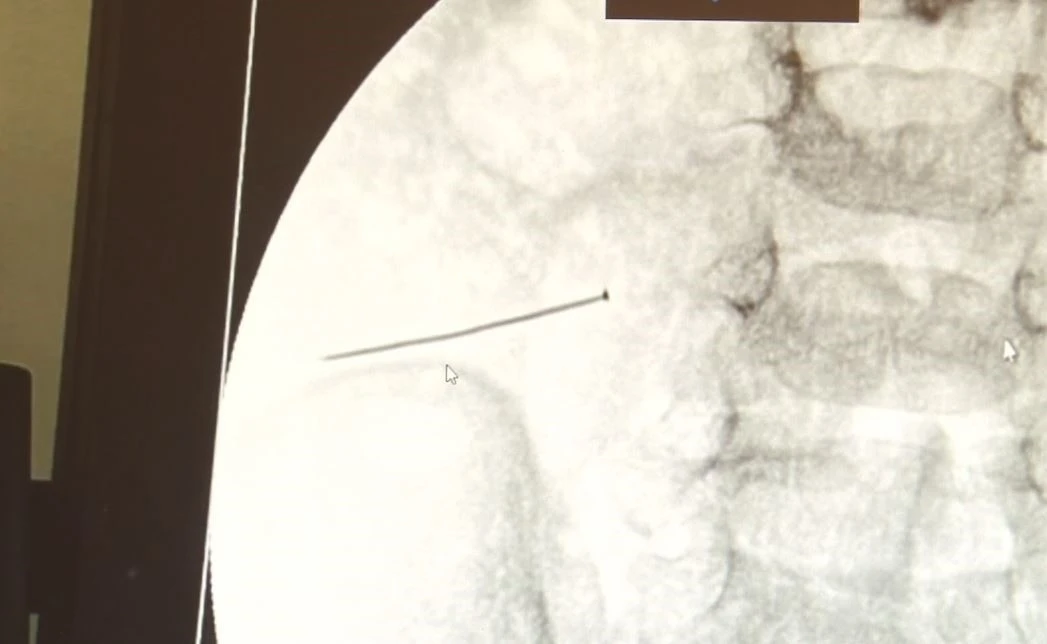

Kocaeli’de 3 yıl önce VM Medical Park Kocaeli Hastanesi’nde uygulanmaya başlanan HoLEP yöntemiyle bugüne kadar 330 hasta tedavi edilerek sağlığına kavuştu. Kapalı teknikle prostat dokusunun lazerle temizlenip morselatör yardımıyla dışarı alınmasına dayanan yöntem, açık cerrahinin getirdiği kanama ve uzun iyileşme süresi gibi dezavantajları ortadan kaldırıyor. Başarıda imzası bulunan VM Medical Park Kocaeli Hastanesi Üroloji Kliniği’nden Doç. Dr. Yaşar Bozkurt, Op. Dr. Adem Tok ve Op. Dr. Cem Alan ile birlikte hastane yönetimi ve tüm cerrahi ekip, 330. vakaları dolayısıyla pasta keserek bu özel anı kutladı. "Tekrar prostatın nüksetmemesi açısından faydalı"

"HoLEP, prostatın kapsülünü bırakarak lazer yöntemiyle sıyırıp mesaneye atmak ve oradan da yine kapalı yöntemle bir morselatör yardımıyla bu içeriye atılan dokuları kıymık haline getirip dışarıya alma yöntemidir. Kanama azlığı, her büyüklükteki bir prostata uygulanabiliyor olması, minimal invaziv bir işlem olması, hastanede kalış süresi, işe dönüş süresi açısından günümüzde altın standart tedavi yöntemi olarak kabul edilmektedir. Bu ameliyat, açık ameliyata alternatif bir yöntem olarak tıp literatürüne girdi. Özellikle kapalı ameliyatta kalan dokunun tamamen temizlenmesi, tekrar prostatın nüksetmemesi açısından faydalıdır." "330 vakalık bir seriye ulaştık"